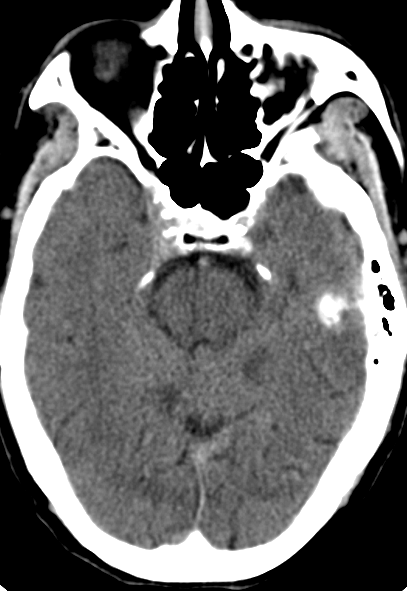

我院头颈CT/CTA:

右侧锁骨下动脉迂曲明显,左侧颈总动脉迂曲,左颈内动脉重度狭窄